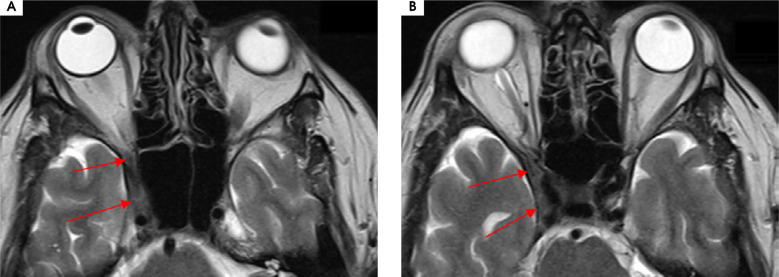

Purpose: Tolosa-Hunt syndrome (THS) is a rare cause of painful ophtalmoplegia with different clinical manifestations. It is described as a unilateral periorbital headache with concomitant dysfunction of at least one out of the IIIrd, IVth and VIth cranial nerves due to the granulomatous inflammation of periorbital structures, but no underlying cause has been established.

Case description: We present six patients referred to the Neurology Department due to a unilateral headache with ipsilateral paresis of at least one cranial nerve responsible for eye movements. The THS diagnostic criteria of the International Headache Disorders Classification (ICHD-3) were applied and analysed. Few patients had atypical clinical manifestations according to these criteria.